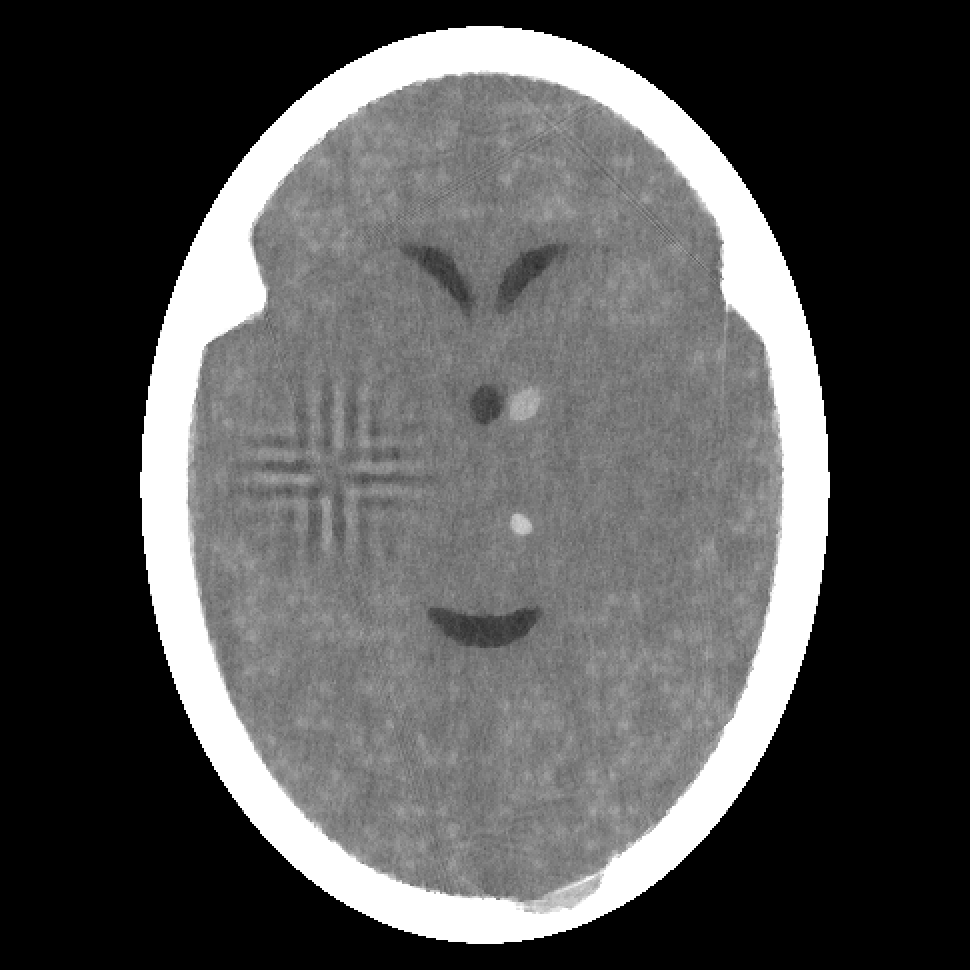

Figure 2: Reconstructions from 180 projections by (a) filtered back-projection, (b) the algorithm ART, (c) TV-Based Superiorized Version of ART, and (d) Shearlet-Based Superiorized Version of ART.

For this anecdotal experiment we use three different numbers of views (i.e., projections): 180, 360, and 720. We emphasize that, in the currently-described anecdotal experiment, there is only one phantom (which provides the ground truth); random generation of local inhomogeneities and of tumor locations is done only once and the same arrangement of local inhomogeneities and of tumor locations is used when generating the projection data for the three different numbers of views.

We present the visual results of the reconstructions produced by these algorithms when using 180, 360, and 720 projections in Figures 2, 3, and 4, respectively. We now give our impressions based on these visual results.

From the results for the single data set with 180 projections (Figure 2), we see that none of the four reconstruction algorithms produces an image in which the small tumors are easily locatable. Furthermore, the Shearlet-Based Superiorized Version of ART introduces high frequency artifacts in the brain near the skull and blurs the features inside the brain. In comparison, both filtered back-projection and ART (to a lesser extent) introduce artifacts in the form of streaks originating from interior bone edges. The image produced by TV-superiorized ART does not show significant high-frequency artifacts, the only one of the four, but the image is blurred.

In the case of 360 projections, the resulting images still show that none of the algorithms provides clear visualization of the small tumors; although they are somewhat visible in the images produced by filtered back-projection and by ART. The Shearlet-Based Superiorized Version of ART still shows high-frequency artifacts, albeit less pronounced than in the case of 180 projections. TV-superiorized ART produces an image in which the features, especially the small tumors, are smoothed out, but the larger features within the brain are clearly identifiable.

As expected, the greater are the number of projections, the better are the reconstructions produced by any of the four algorithms. However, even with 720 projections, the reconstruction produced by the Shearlet-Based Superiorized Version of ART still shows some high-frequency artifacts and the small tumors are less visible than in the images produced by the other three algorithms.